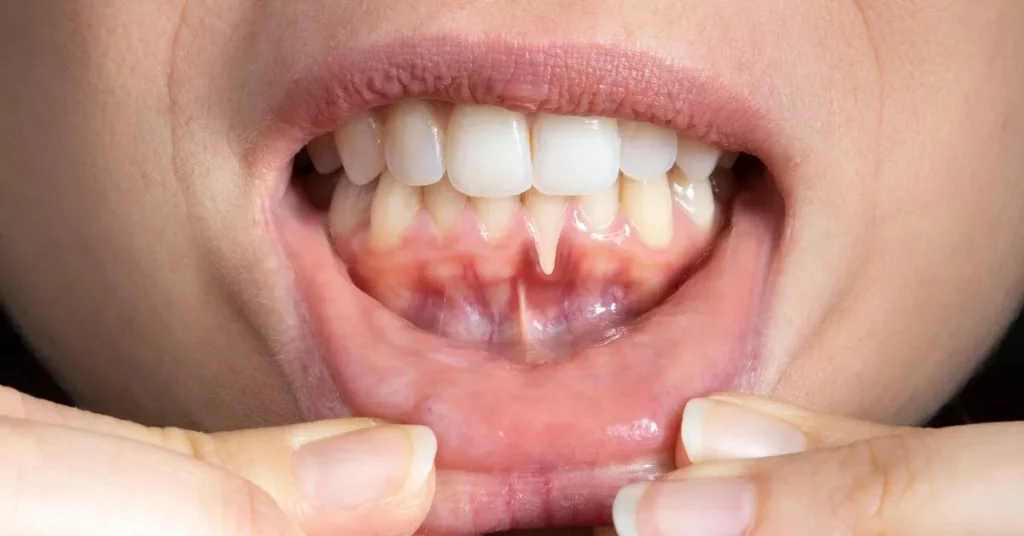

Encía retraída en un solo diente

Puede ocurrir por:

Traumatismo por cepillado

Malposición dental

Fuerzas excesivas al morder

Frenillos insertados cerca de la encía

En estos casos, el tratamiento suele ser más localizado y conservador.